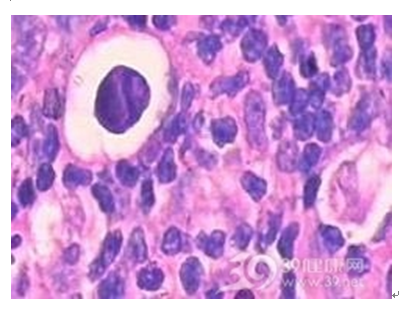

慢性淋巴结炎

慢性淋巴结炎多继发于头、面、颈部的炎症病灶。淋巴结不同程度的肿大,散见于颈侧区或颌下、颏下区。可略硬但表面光滑,能活动,可有轻度压痛或不适。慢性淋巴结炎本人不需要治疗,检查时应注意寻找原发炎症灶。除颈部各区外还应仔细检查头皮、外耳及口腔、扁桃体、牙龈等隐藏部位。还可按肿大淋巴结的淋巴接纳区找寻原发病灶。